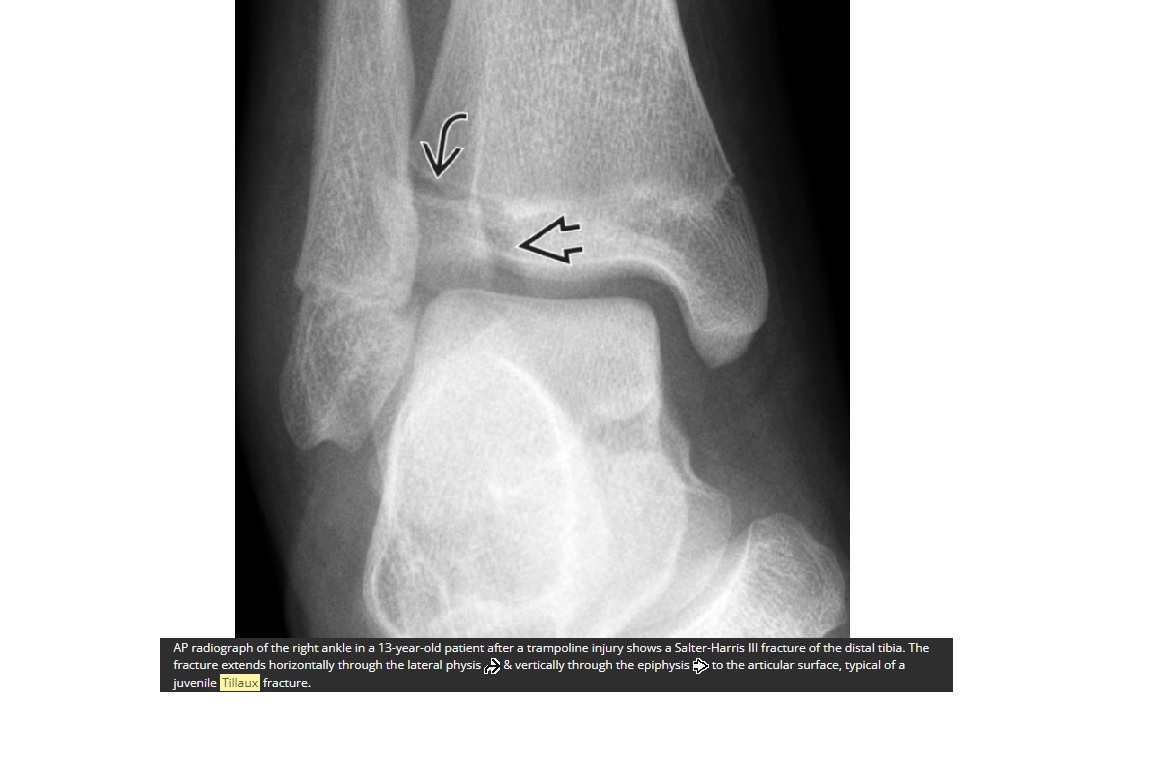

What is tillaux fracture?

A

Salter-Harris 3 = through the anterolateral distal tibial epiphysis

How well did you know this?